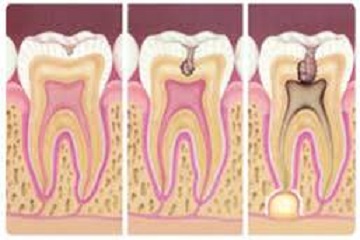

A konzerváló kezelések körébe azok a fogászati beavatkozások tartoznak, melyek az ép fogak megörzését szolgálják.